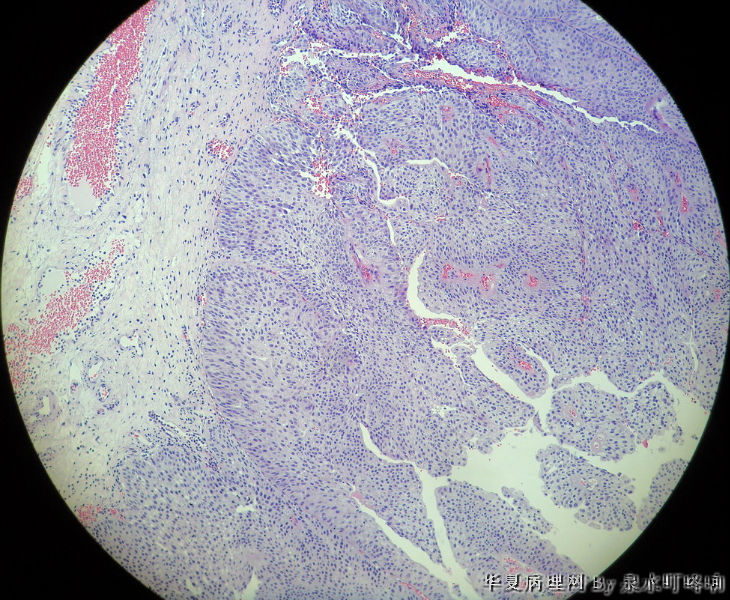

膀胱肿物

膀胱肿物图4

名称:图4

描述:4

男,76岁,血尿一个月,发现膀胱肿物,行切除术,肿物位于右侧膀胱后外侧壁,约1.5×1.5×1.5厘米。

大体:灰白肿物一个,大小约2×1.1×0.9厘米,切面灰白,质中。

尿路上皮癌,低级别。

低级别非浸润性乳头状尿路上皮癌

(膀胱)非浸润性乳头状尿路上皮癌,低级别

低级别尿路上皮癌。至于浸润的问题还请楼主仔细观察切片,总感觉那种推进式的生长模式有浸润的嫌疑,临床上浸润与否治疗方式是不一样的。

Dx: High grade papillary urothelial carcinoma because: 1. nuclear chromasia (fig 13) and coarse chromatin. 2, almost all nuclei have prominent  nucleoli. 3, Nuclear pleomorphism (some nuclei are three times larger than smaller ones). 4. Nuclear membrane irregularity. 5. mitosis can be seen far away from the basement membrane. 6. a good portion of the neoplastic cells loss orientation that should be perpendicular to the basement membrane. 7. Low power view shows papillary branching and fusion. 8. patient's age

However, this should be the low end of the spectrum of high grade urothelial carcinoma. Careful search might reveal some focal microinvasion.or urothelial carcinoma in situ.